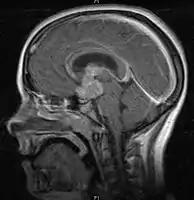

CNS Germinoma

- Mainly located in midline structures, suprasellar region or pineal gland, also basal ganglia and hypothalamus

Location

- Pineal Gland Germinoma

- Suprasellar Germinoma